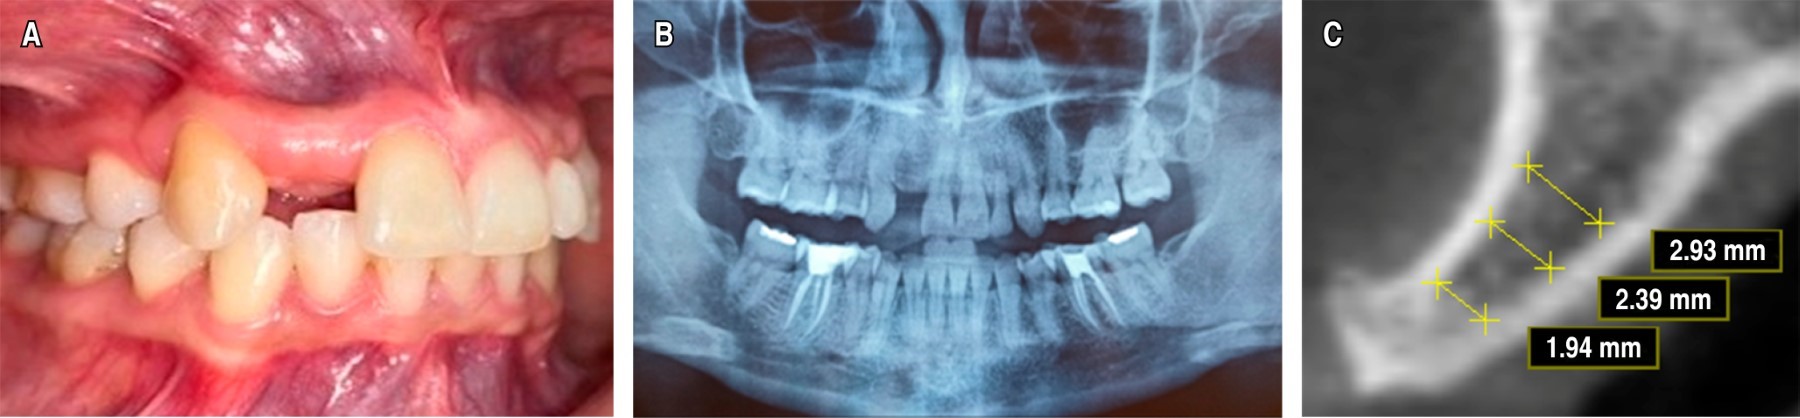

Caso 1: al Servicio del Postgrado de Cirugía Bucal de la Universidad Central de Venezuela (UCV), asistió paciente femenino de 34 años de edad, sin antecedentes médicos que contribuyeran al caso, para evaluación y planificación de implante dental por espacio edéntulo en zona anterosuperior, no reporta sintomatología asociada a su motivo de consulta. Se realizó su historia clínica, consentimiento informado y su autorización para el uso de registro fotográfico con fines académicos y divulgación científica. En el examen clínico intrabucal e imagenológico, mediante una ortopantomografía de mediana calidad técnica, se evidenció agenesia del órgano dentario (OD) 12 (Figura 1A y B), se solicitaron estudios complementarios como tomografía computarizada de haz cónico (Cone Beam), en donde se observó, en un corte transaxial, deficiencia ósea en sentido horizontal en reborde alveolar de la zona del OD 12, con unas dimensiones de 1.94 mm en sentido vestíbulo-palatino en su porción crestal y 2.93 mm en sentido vestíbulo-palatino en su porción más cefálica (Figura 1C).

Una vez evaluados y comparados los hallazgos clínicos e imagenológicos, se estableció como diagnóstico agenesia del OD 12 con deformidad del reborde alveolar anterior grado I Seibert en la zona del OD 12. Se planteó el tratamiento en dos fases quirúrgicas, en la primera, la colocación de un injerto autólogo en bloque tomado de la zona de mentón para reconstruir el defecto y, posteriormente, una segunda fase para la colocación del implante dental en posición del OD 12.